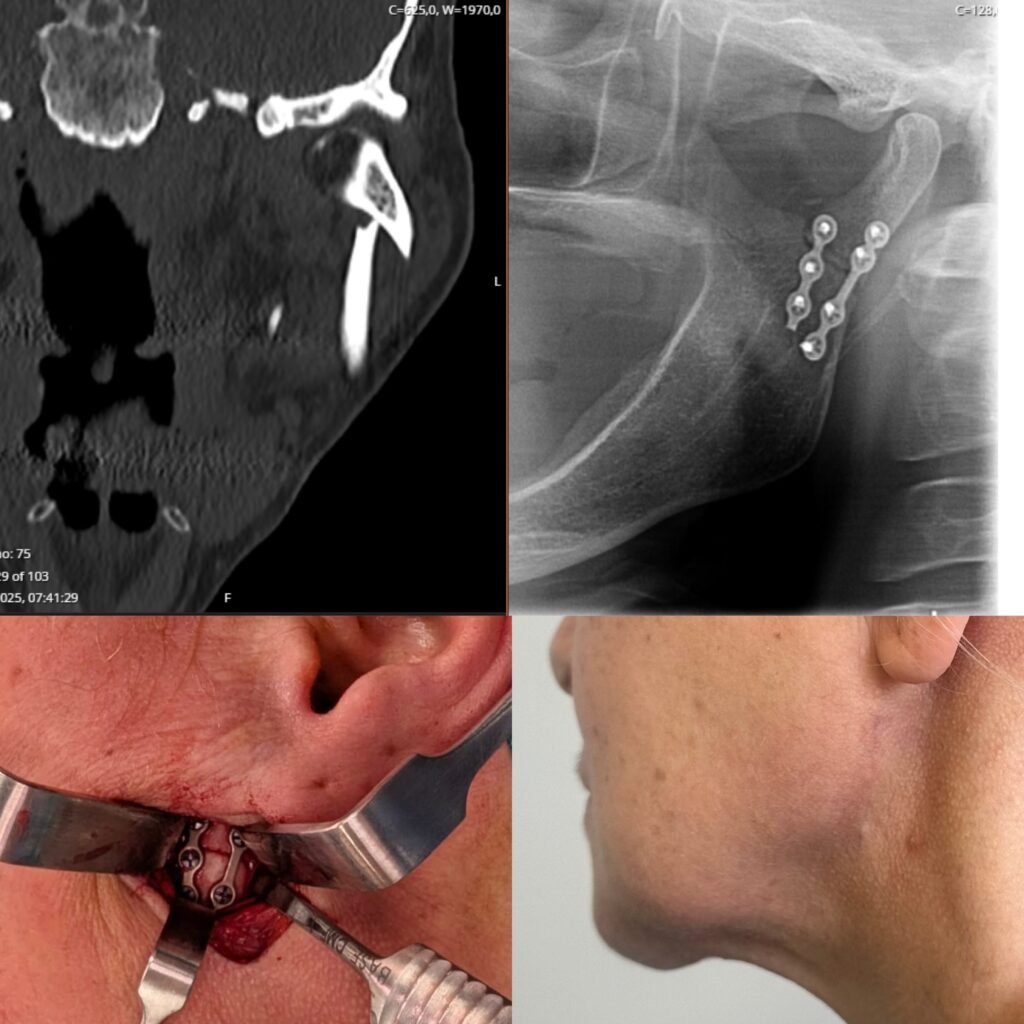

Uma fratura de ossos faciais ocorre quando um ou mais ossos da face se partem devido a um traumatismo, como um acidente, uma queda ou um impacto direto. As fraturas podem afetar os ossos das órbitas, malar ou arco zigomático, nariz, maxila ou mandíbula.

O objetivo da cirurgia irá passar pela redução da fratura (“realinhar” os ossos). Em alguns casos, esta é combinada com osteossíntese, que consiste na fixação do osso na posição correta com placas e parafusos. A cirurgia é realizada sob anestesia geral.

Casos